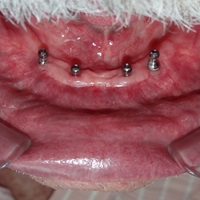

• Implanty jako zakotwiczenie protezy częściowej i całkowitej

Nie u każdego pacjenta można wykonać stałe odbudowy protetyczne oparte na implantach. Powody najczęściej sa prozaiczne, takie jak koszty, niekorzystne początkowe warunki kostne i wymagane rozległe odbudowy kości, strach przed bólem a także - jakże często - zdrowy rozsądek. Wiadomo bowiem, że w przypadku rozległych, trudnych technicznie do wykonania regeneracji kostnych zwiększa się obciążenie organizmu, oraz możliwości wystąpienia powikłań, a więc zwiększa się ryzyko niepowodzenia w leczeniu. Dlatego wykorzystujemy implanty jako zakotwiczenie atachmentów do utrzymania protezy ruchomej. Takie rozwiązanie pozwala na zmniejszenie kosztów, ograniczenie zakresu zabiegu, oraz co najważniejsze pozwala na poprawę jakości życia i zadowolenia z użytkowania protez ruchomych.

Pacjentka głosiła sie do naszego gabinetu do leczenia z osadzonym mikroimplantem w pozycji lewej dolnej dwójki. Siostrzany implant w pozycji prawej dolnej dwójki wypadł wcześniej, około 1,5 roku od implantacji. Odtworzono przedsionek i dziąsło rogowaciejące, osadzono dwa implanty, jednoczasowo z regeneracją kości. Dopiero na etapie ostatecznej rekonstrukcji protetycznej usunięto zachowany mikroimplant. To się nazywa motywacja do leczenia! Pacjentka przygotowywała sie na ślub prawnuczki :)